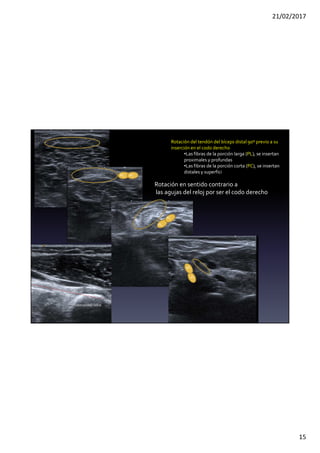

Rotación del tendón del bíceps distal 90º previo a su

inserción en el codo derecho

•Las fibras de la porción larga (PL), se insertan

proximales y profundas

•Las fibras de la porción corta (PC), se insertan

distales y superfici

Rotación en sentido contrario a

las agujas del reloj por ser el codo derecho